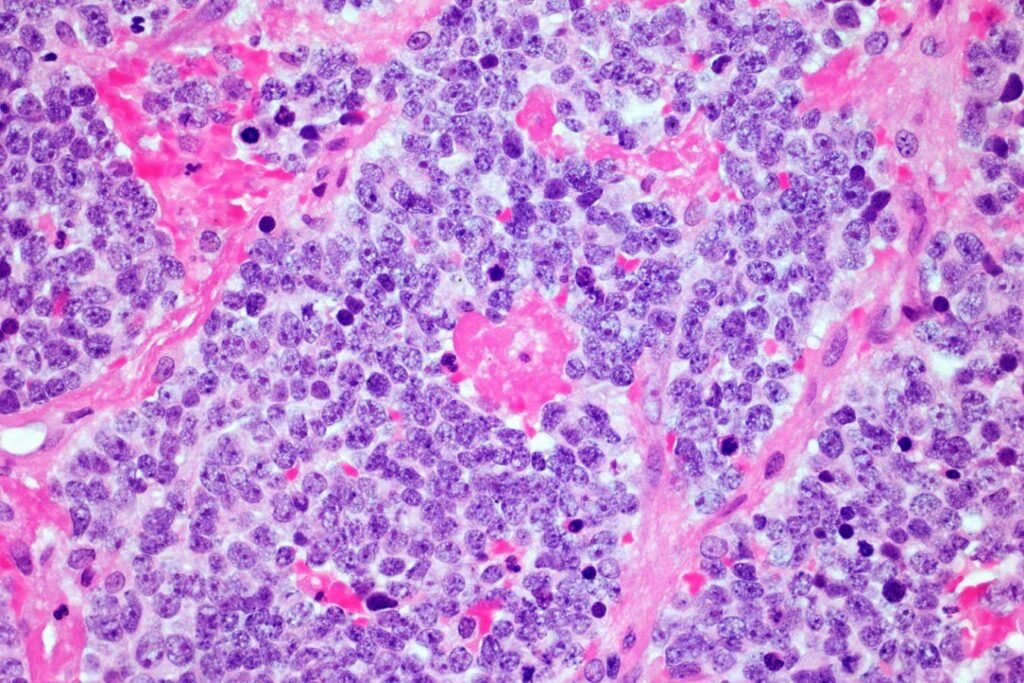

Microscopic image of a neuroblastoma tumor

The car t-cell therapy fails against strong tumors such as neuroblastoma when they become cancer when developing nerve cells in children, usually before 5 years. Such tumors are very hard to maintain the immune system, changed T-cells.